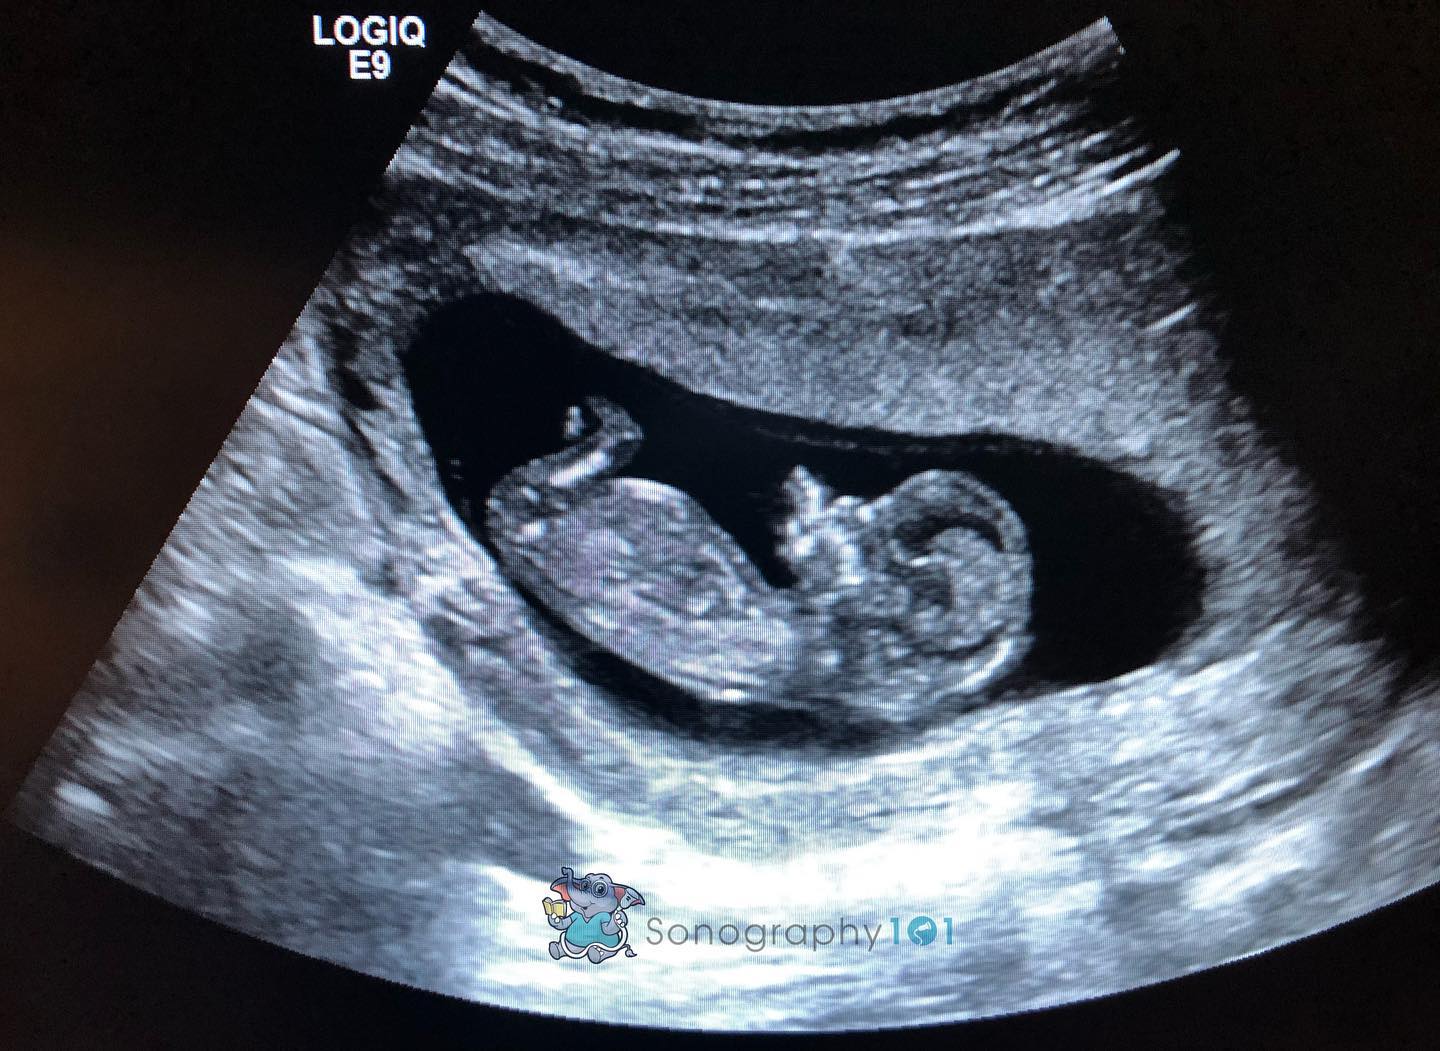

Recent Blogs